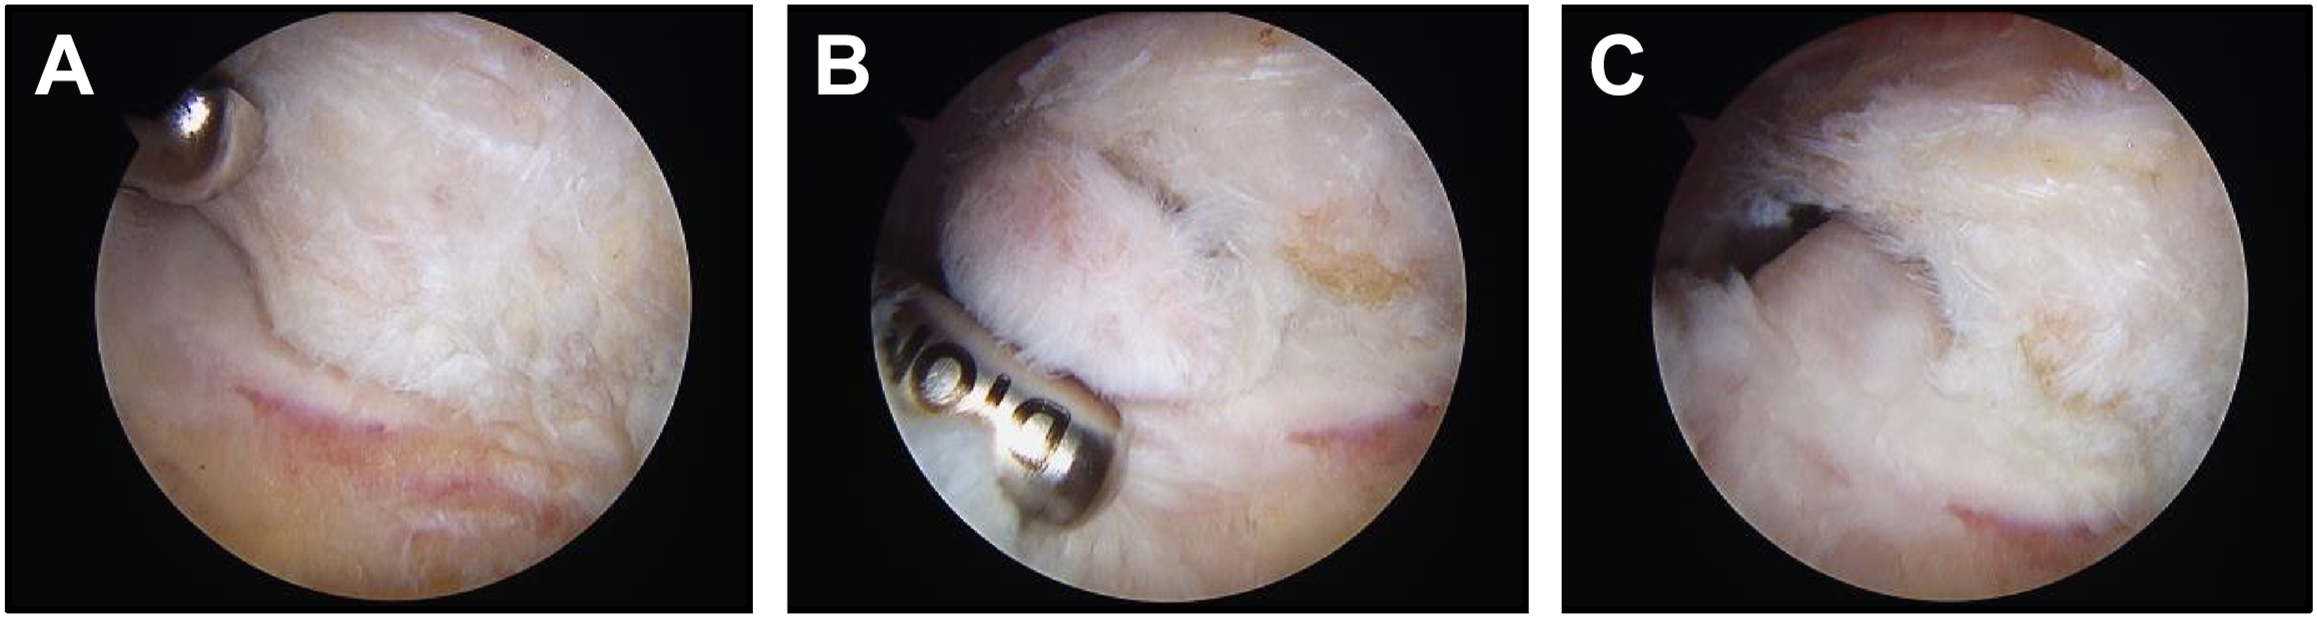

Surgical intervention for VEOS is indicated when throwers fail to obtain symptom relief after a trial of conservative management. Arthroscopic posteromedial debridement and osteophyte excision have ultimately become a safe and reliable method to treat VEOS in throwers, with many results demonstrating high patient satisfaction and high rates of return to play (RTP). , , , , Andrews and colleagues first demonstrated an RTP rate of 70% at 24 months in 56 professional baseball players with posterior osteophyte excision; however, 41% required reoperation for repeat debridement. Five years later, Reddy and colleagues showed an RTP rate of 85% in baseball players undergoing arthroscopic treatment of posterior impingement. More recently, Koh and colleagues and Matsuura and colleagues both demonstrated RTP rates as high as 97% and 100% in 36 and 15 throwers, respectively, undergoing elbow arthroscopy with posteromedial olecranon osteophyte resection. It is important to note, however, that olecranon spurs are routinely found in asymptomatic throwers (especially professional baseball players), and thus posteromedial decompression is only indicated in patients with positive provocative testing.

Historically, the goal of surgical management for posteromedial impingement was to resect the olecranon tip in its entirety. However, modern thought and techniques now advocate against the removal of any portion of the normal olecranon margin ( Fig. 2 ). Kamineni and colleagues first demonstrated that sequential partial resection of the posteromedial olecranon resulted in a stepwise increase in valgus angulation as the amount of resection increased in 12 cadaveric elbows, challenging the rationale of removing any amount of normal olecranon in throwing athletes. In a follow-up study, Kamineni and colleagues demonstrated increased strain on the MUCL with olecranon resections greater than 3 mm, supporting MUCL insufficiency as a relative contraindication to posteromedial decompression in fear of exacerbating valgus instability. Paul and colleagues validated this fear by reporting that 18% of 28 baseball pitchers that underwent isolated arthroscopic posteromedial osteophyte resection for posteromedial impingement went on to require MUCL reconstruction surgery.

Overall, the goal of arthroscopic debridement in throwers with VEOS should be restoration of the normal contour of the posteromedial compartment without removal of any portion of the normal olecranon margin, along with concomitant procedures of MUCL reconstruction or ulnar nerve transposition as indicated. It is critical to work up and recognize MUCL injury and valgus laxity in these patients in order to not worsen medial-sided pain and instability in the future. Advances in instrumentation and arthroscopy technique continue to improve the safety and efficacy of elbow arthroscopy in throwers. Surgeon’s experience, knowledge, strategic preoperative planning, and expectation management remain paramount in the treatment of these athletes.